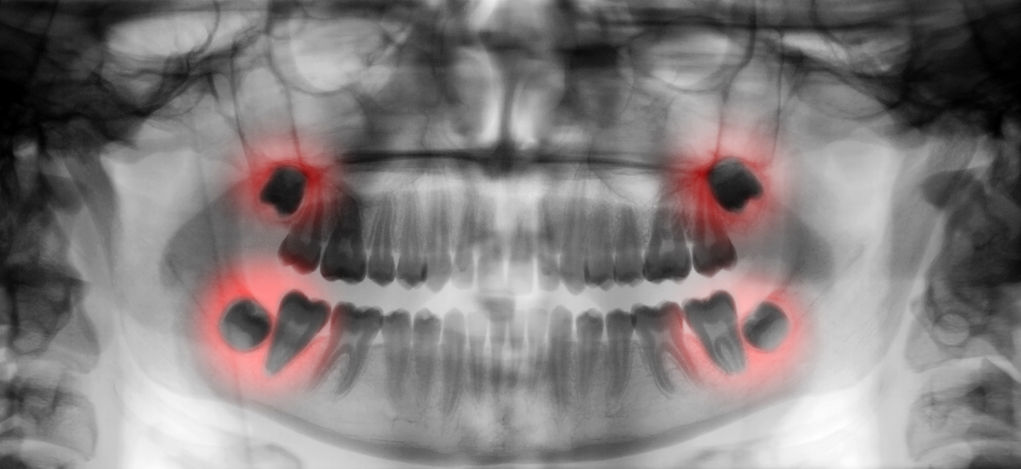

Your third molars are more commonly called "wisdom teeth." Usually appearing in the late teens or early twenties, third molars often lack the proper space in the jaw to erupt fully or even at all. This common condition is called impaction. When any tooth lacks the space to come through or simply develops in the wrong place of your jaw and becomes impacted, problems can arise. Primarily, damage to adjacent teeth and crowding occur.

In certain cases, the wisdom tooth that cannot come through becomes inflamed under the gums and in the jawbone, causing a sac to develop around the root of the tooth that then fills with liquid. This can cause a cyst or an abscess if it becomes infected. If either of these situations goes untreated, serious damage to the underlying bone and surrounding teeth and tissues can result. (Insert photo named impacted teeth in this segment)